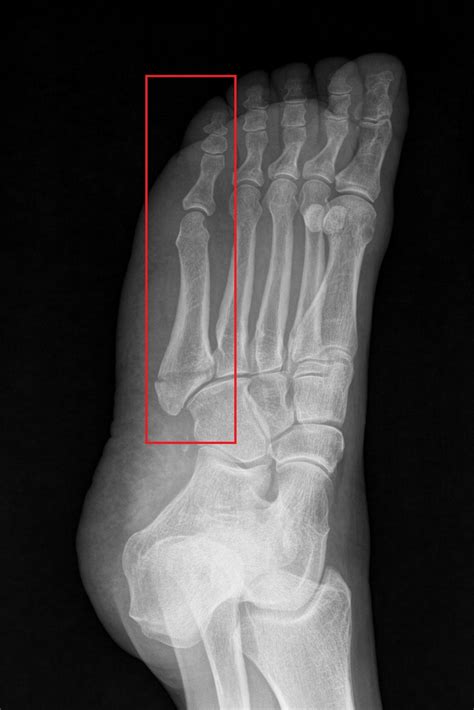

• X-Rays: X-rays are the primary imaging tool used to confirm the presence and location of the fracture.

• pictures of 5th metatarsal fracture